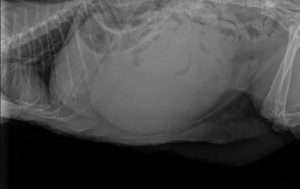

The X-ray in fact showed an extremely dilated bladder, which occupied most of the abdominal cavity.

The visible uterus suggested pyometra.